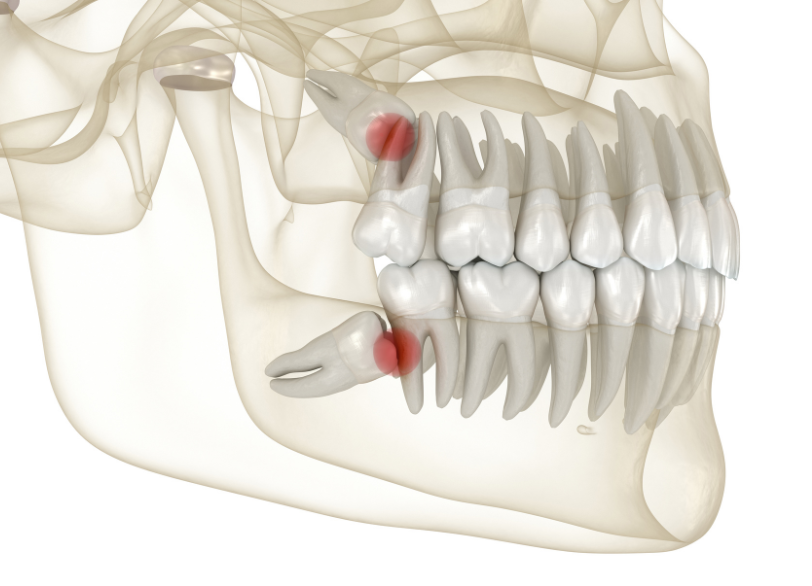

十分なスペースがないために、親知らずは様々な不自然な生え方をしてしまいます。

- 斜めに生える

- 横向きに生える(水平埋伏)

- 一部だけが歯肉から出ている(半埋伏)

- 骨の中に完全に埋まっている(完全埋伏)

このような不自然な生え方をすると、お口の中に様々なトラブルを引き起こす原因となります。

特に、下の親知らずのすぐ近くには「下歯槽神経(かしそうしんけい)」という、下唇の感覚などを司る非常に重要な神経が通っています。

従来の二次元のレントゲン写真だけでは、この神経と親知らずの根との正確な位置関係を把握することは困難です。

当院では、抜歯の前に必ず歯科用CTによる撮影を行いこの神経と歯の根との距離や位置関係を、三次元的にそしてミリ単位で正確に把握します。

この情報を基に、神経を傷つけるリスクを限りなくゼロに近づけるための安全な抜歯計画を立案します。